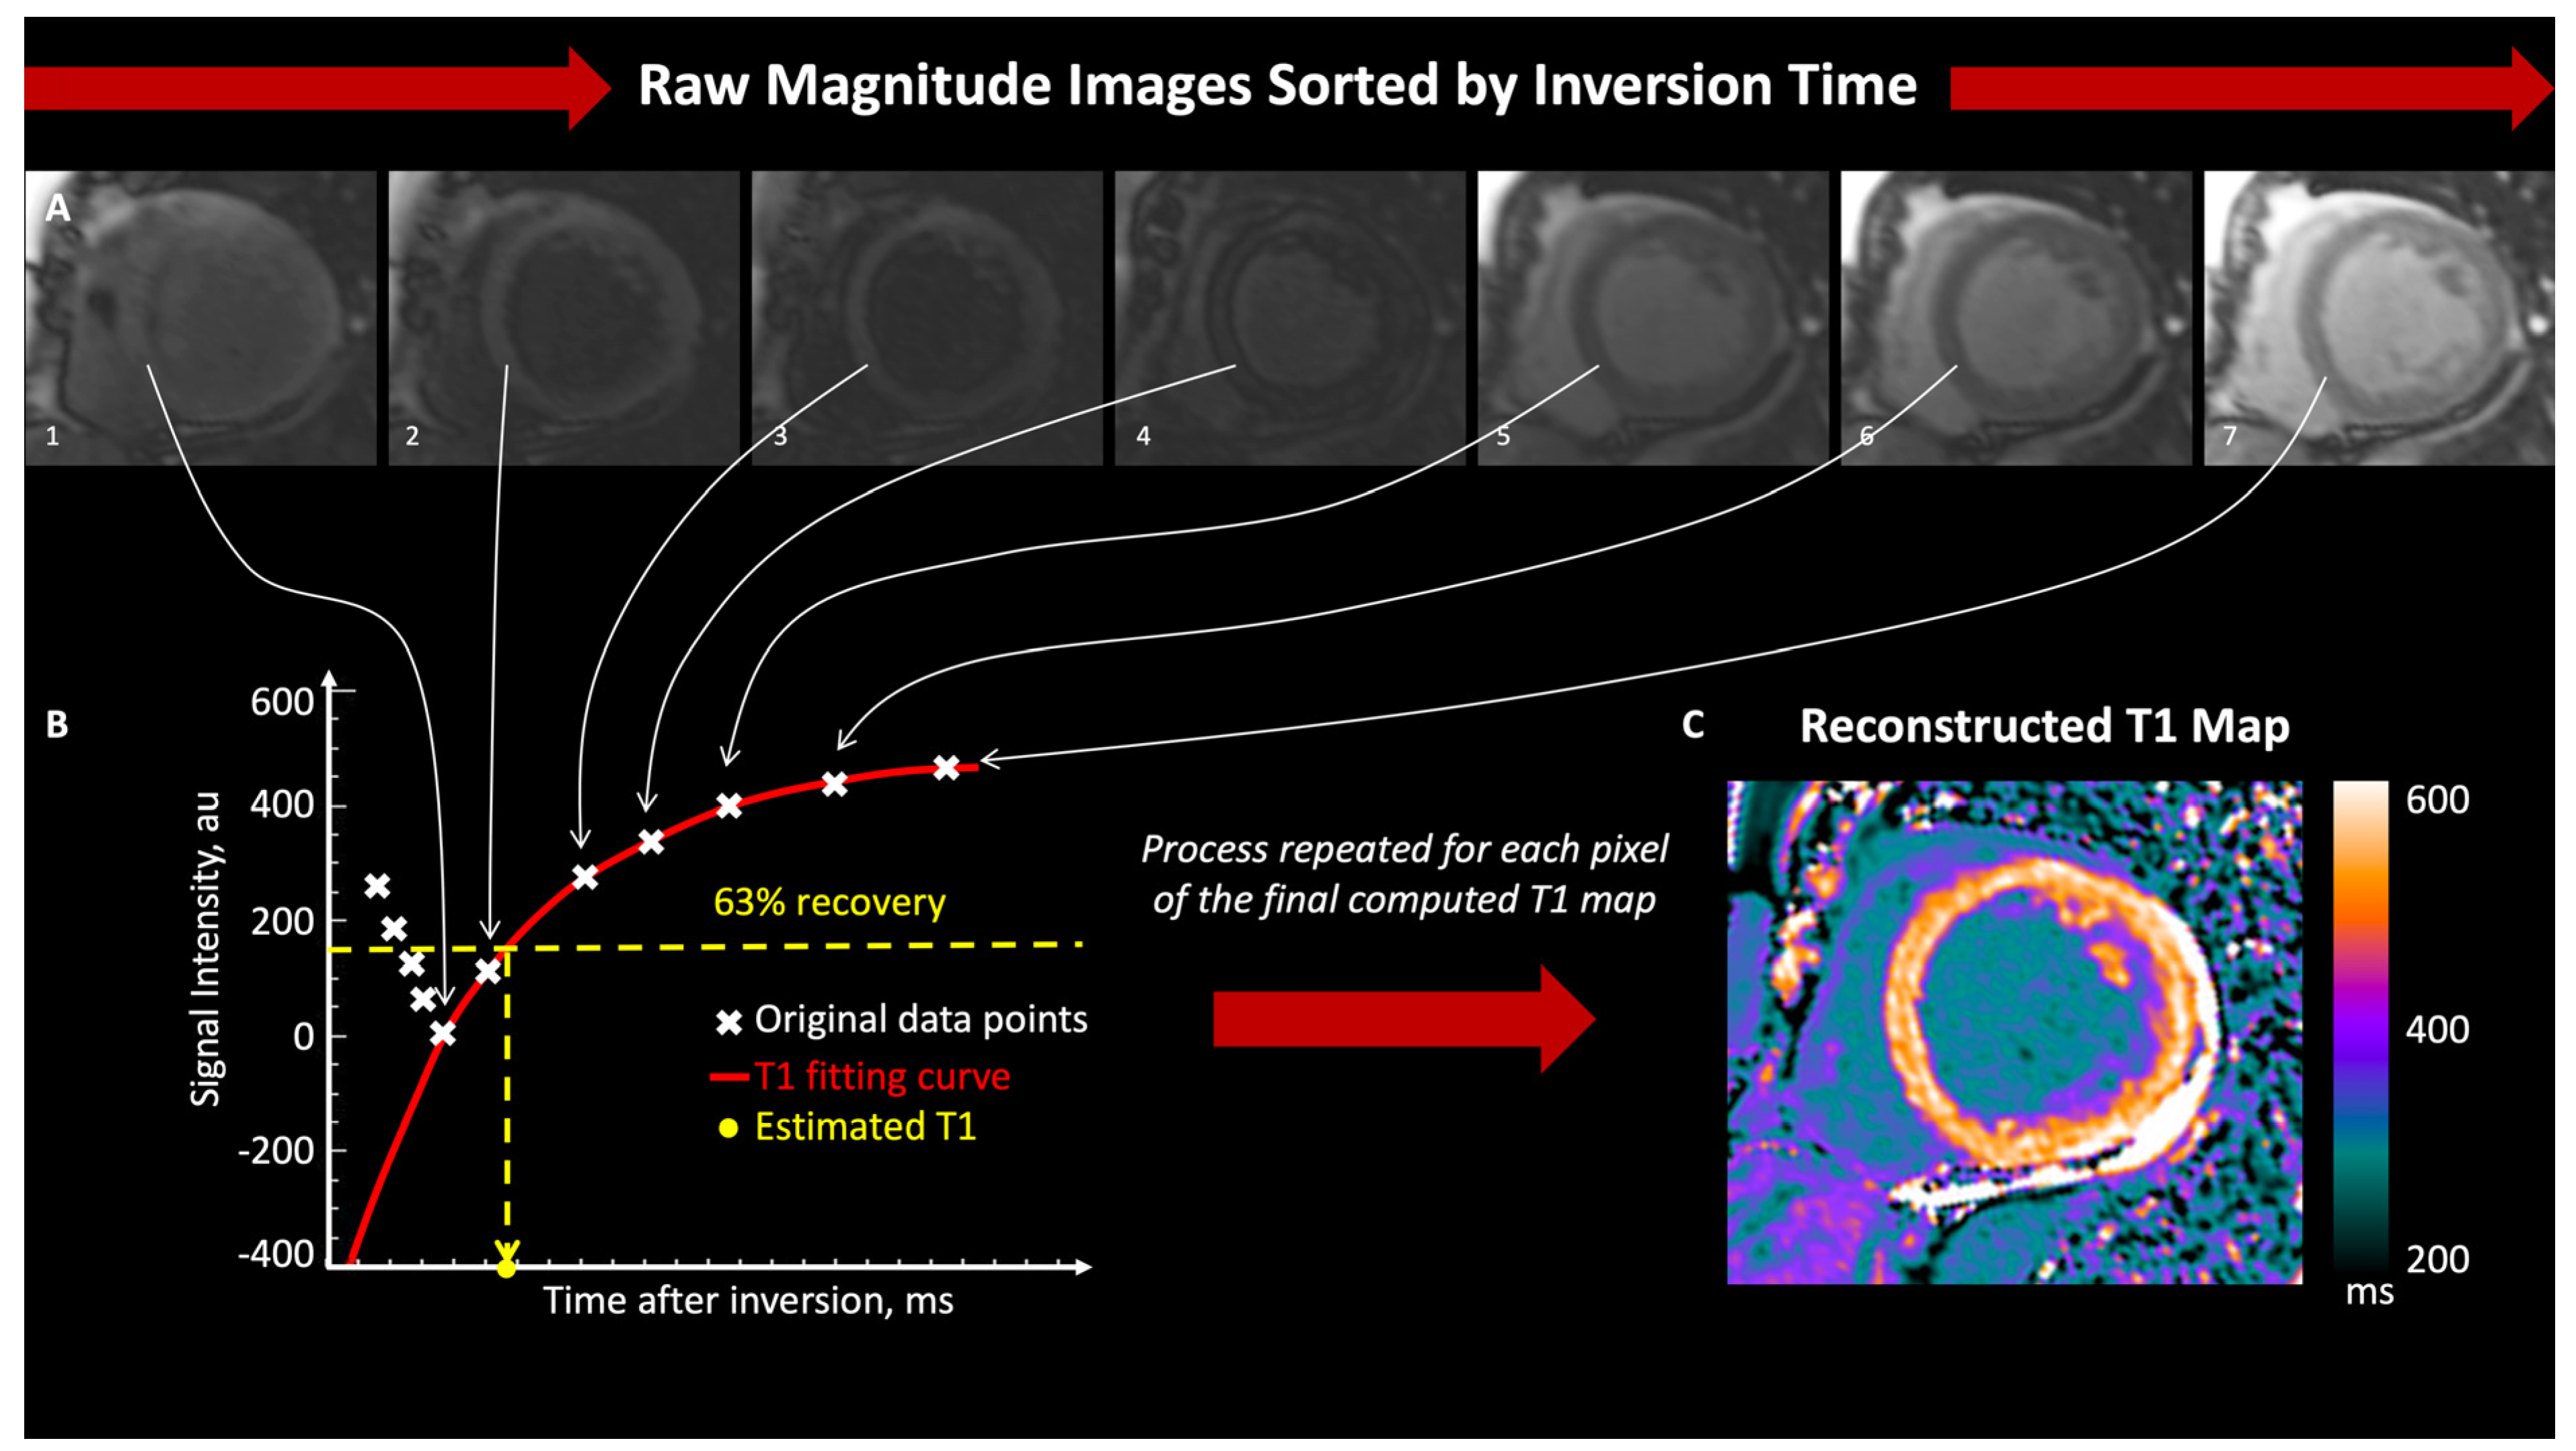

2. Physical Principles

3.1. T1 Mapping